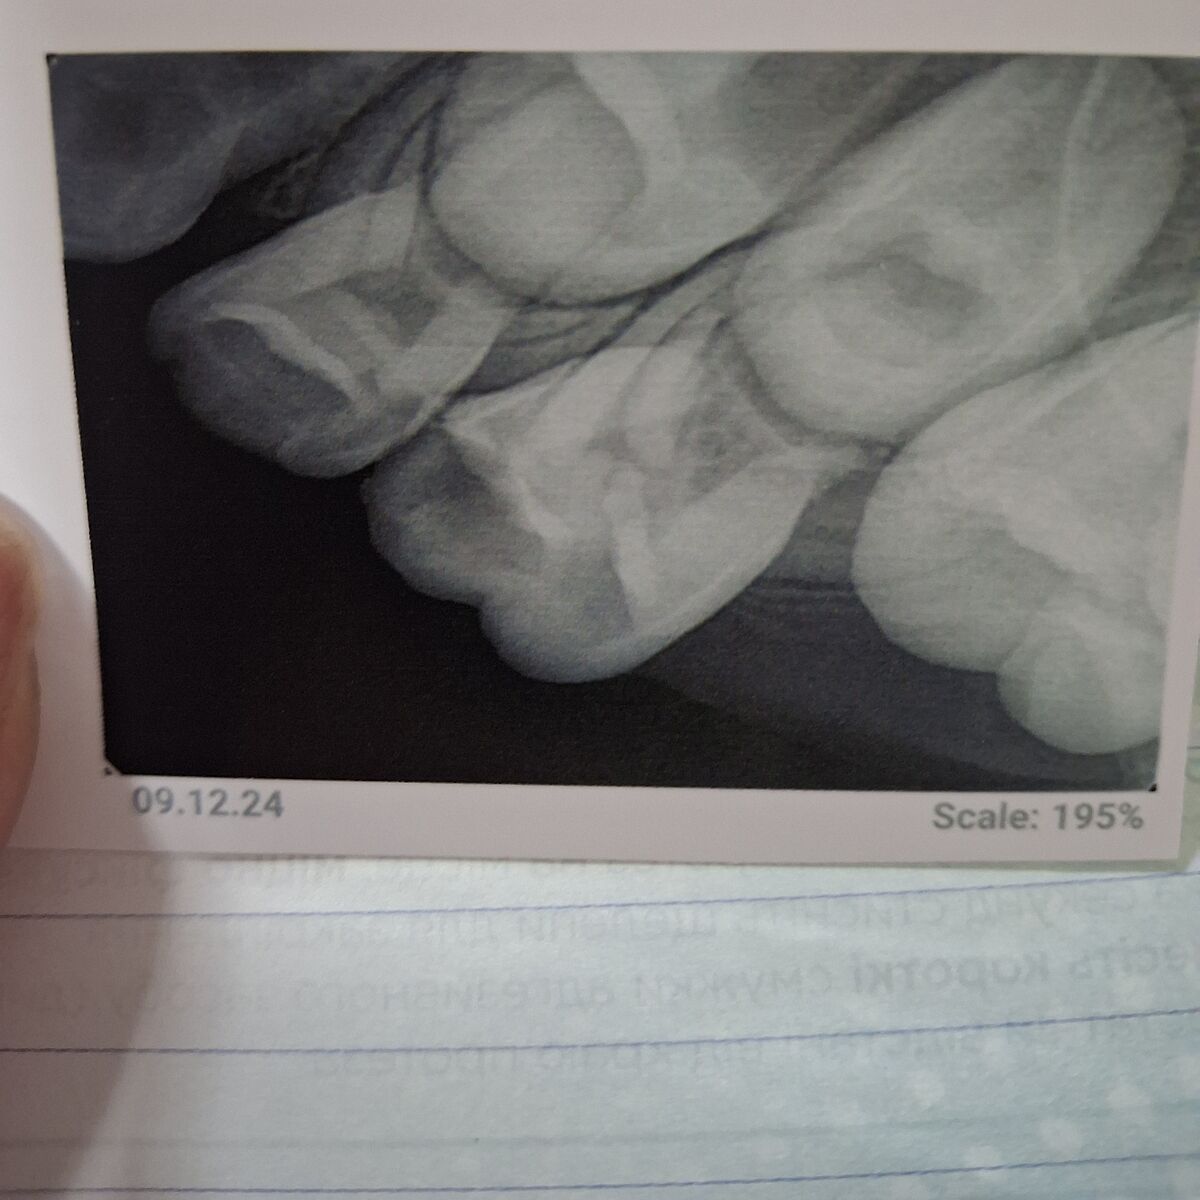

Стоматологи, можете глянуть рентген?

6 лет, зуб болит при жевании. Под вопросом 4ка или 5ка. Что там?

В 5 глубокий кариес, возможно пульпит, но в 4 можно вскрыться во время прпаровки, так как рога пульпы близко и коронка сама меньше.

Болит при жевании, потому что пищевой комок давит на десну.